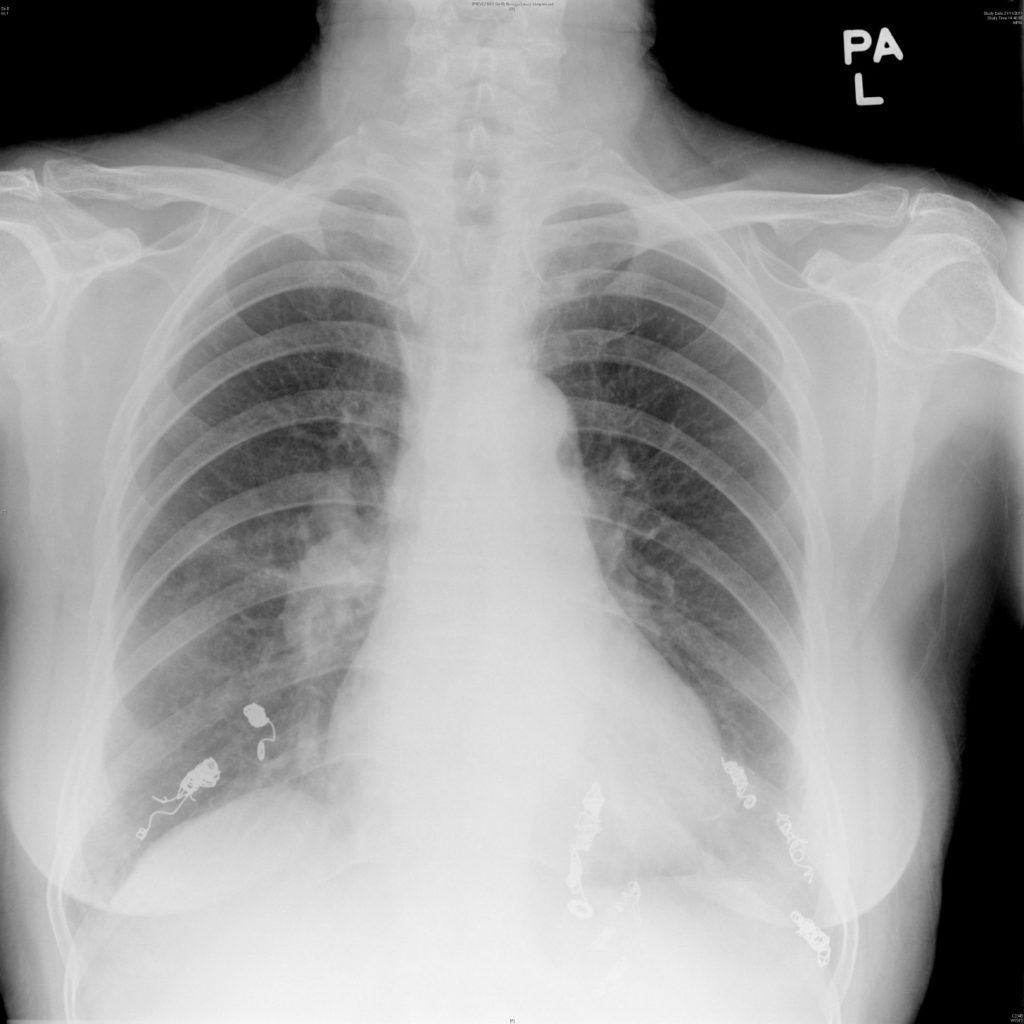

Four sessions of embolization therapy were performed by radiologist in Princess Margaret Hospital from May 2011 to Nov 2011. Antibiotic prophylaxis was given before each session to prevent cerebral abscess. Echocardiogram was also arranged after each session of embolization therapy. So far, findings were quite similar to her pre-procedure ones and no pulmonary hypertension was demonstrated. With successful embolization therapy, she was able to gradually tail down and eventually wean off oxygen supplement with room air SpO2 93-95% afterwards. Follow-up computer tomography scan was arranged 6-12 months after the last embolization for monitoring in addition to regular outpatient visit.

Finally, screening of PAVM is mandatory in all HHT patients according to international guideline 200914. Chest X-rays and contrast echocardiography were recommended to be the initial investigation of choice with sensitivity up to 100% combining the two15. Computer tomography is important in delineating the architecture of PAVM before embolization therapy, follow-up to detect growth of untreated PAVM and reperfusion of treated lesions.

Figure 3: embolization therapy and patient’s latest chest X-rays after total 4 sessions of procedures